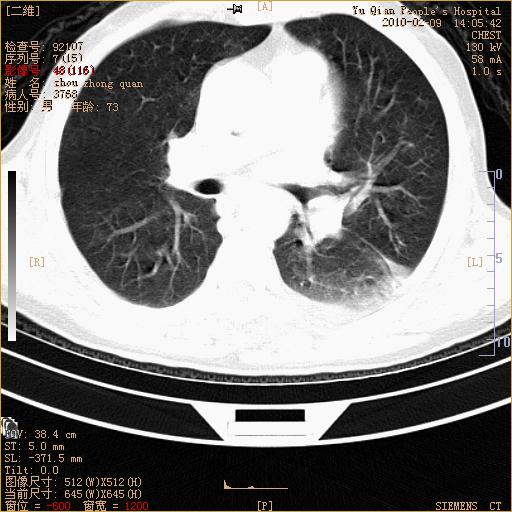

男性,73岁,咳嗽咳血数天,诊为肺ca伴左肺下叶后段阻塞性炎症、肺不张妥否?

右下肺有转移?

左下肺中央型肺癌伴结段形肺不张,左侧胸腔积液,纵隔内见部分增大淋巴结(反应性增生或转移)

左下基底干支气管明显变窄。

左肺下叶基底段支气管狭窄,左肺门增大,左肺下叶团片状病灶。中心型肺癌伴柱塞性炎症可能大,建议支气管镜检查。

左下肺中央型肺癌伴节段性肺不张,左侧胸腔积液,纵隔内见肿大淋巴结

左下基底段支气管变窄。建议进一步纤支镜检查。

1、左肺下叶后基地段肺癌伴阻塞性炎症,左下肺门淋巴结转移。2、左侧胸腔积液。